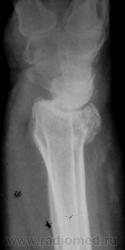

Травма. Пациент направлен на рентгенографию лучезапястного сустава.

луча в типичном месте. А вот шиловидный отросток похоже тоже сломался?